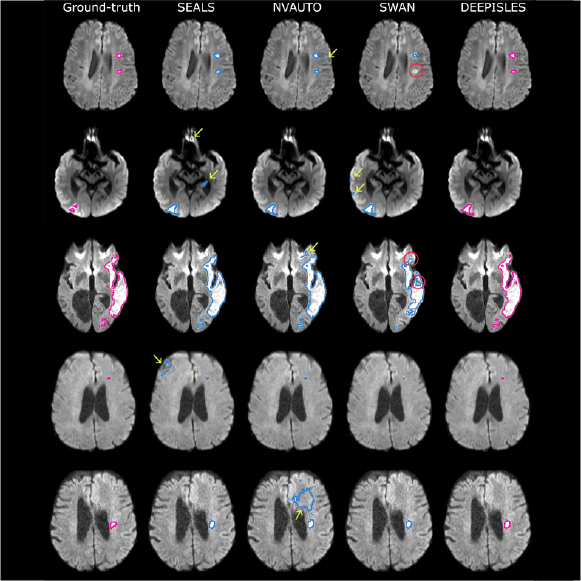

DeepISLES sets new benchmark for stroke MRI segmentation

A DQBM-supported study introduces DeepISLES, a clinically validated AI tool for ischemic stroke lesion segmentation, developed from the ISLES’22 challenge. The algorithm outperforms existing methods in accuracy, generalization, and clinical relevance.